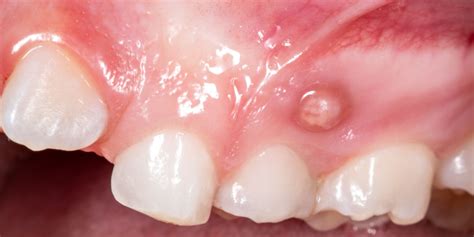

- Dolor e inflamación: Una de las primeras señales de una fístula dental es el dolor en la zona afectada. El dolor es uno de los síntomas más característicos de una fístula dental. Puede manifestarse como un dolor punzante, pulsátil o constante en el área del diente afectado. Este dolor puede empeorar al masticar, hablar o aplicar presión sobre el diente comprometido. Al principio, las encías se inflaman ligeramente y enrojecen. Con el tiempo, la fístula dental se llena de pus y aparece un dolor punzante. Si se aplica mucha presión, el pus drena hacia la cavidad oral.

- Abscesos dentales: La presencia de una fístula dental puede dar lugar a la formación de abscesos dentales. Un absceso dental es una acumulación de pus causada por una infección bacteriana en el tejido dental. En el caso de una fístula dental, el absceso puede manifestarse como una protuberancia roja y dolorosa en las encías cerca del diente afectado. Esta protuberancia puede estar acompañada de sensibilidad al tacto y al calor, así como de hinchazón en el área circundante.